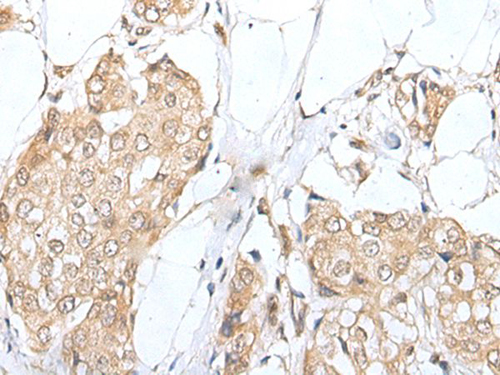

IHC (Immunohistochemistry)

(The image on the left is immunohistochemistry of paraffin-embedded Human esophagus cancer tissue using ZNF263 Antibody at dilution 1/40, on the right is treated with fusion protein. (Original magnification: x200))